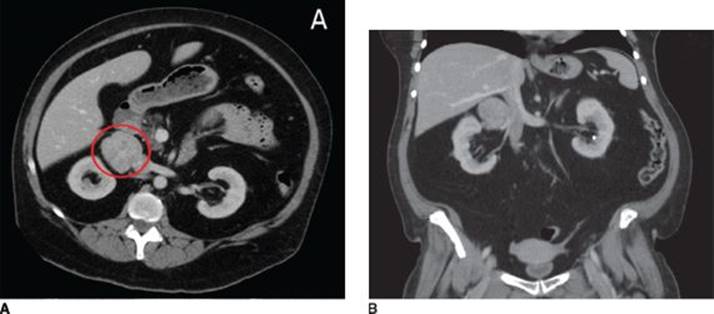

Imaging of the adrenal gland will then help to differentiate an adrenal tumor from bilateral adrenal hyperplasia. If on CT a discrete tumor is visualized, specific CT protocols can be used to further distinguish a benign adenoma from a malignant adrenocortical carcinoma. Benign adrenal tumors tend to have low attenuation on unenhanced images due to high lipid content. Both benign and malignant tumor will enhance with IV contrast; however, after a 10-minute post-contrast administration period, washout in excess of 50% is seen in benign lesions. In our patient, CT scan of the abdomen demonstrated a 5.3-cm contrast enhancing mass in the right adrenal gland (Figure 1).

FIGURE 1 • A: CT scan of the abdomen demonstrating a contrast-enhancing mass in the right adrenal gland (circled). B: Coronal reformatting depicting the relationship of the mass to the right renal vein and the inferior vena cava.